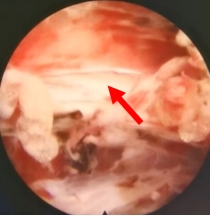

为了保证治疗效果的同时将手术风险降到最低,通过详细的评估和术前讨论,王新涛带领团队选择运用微创的方法。术中,首先用经皮椎间孔镜切除了压迫硬膜囊和神经的增生骨质和肥厚的黄韧带,摘除了突出的椎间盘,椎间孔镜下能看到硬膜囊搏动良好,神经根受压得到解除,随后应用经皮椎体成形手术,向骨折椎体内注入骨水泥,恢复了骨折椎体的高度,增加了骨质的强度。手术完成后仅留了几个不足1厘米的小口,术后当天疼痛就基本缓解,术后第一天患者就能下地行走,取得了满意的结果。王女士高兴的说道:“我原来一动弹就疼,已经在床上躺了好久了,早点来做手术,我早就能下地了,就不用受那么长时间的罪了。”

椎间孔镜下可见神经根受压解除